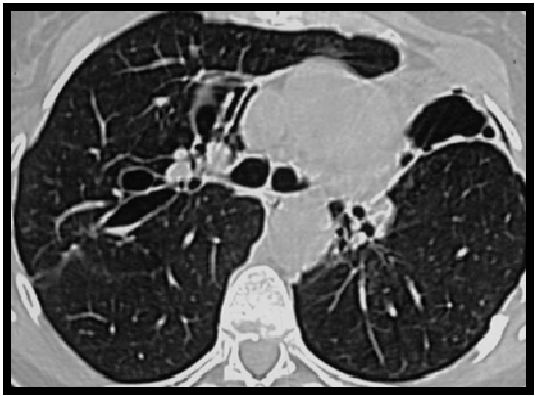

CT扫描显示:(早期IPA)小结节和/或小的胸膜,楔形改变,周围有磨玻璃光晕(晕征)。晕征代表肺泡出血。

随着疾病的进展,结节可能会出现空洞,坏死的薄壁组织会从邻近的肺部分离,形成类似于曲霉菌中所见的空气新月形。

在正确的临床环境中,由磨玻璃晕环绕的结节或实变,进展为空洞或空气新月征,形成被认为是典型的血管侵袭性曲霉菌病。

图13:宫颈癌化疗后子,严重中性粒细胞减少症患者的侵袭性肺曲霉病。MDCT扫描显示双侧多个不明确的结节,伴有外周磨玻璃改变,中叶外侧段的实变区域,也被磨玻璃改变区域包围。